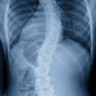

Willkommen im Skoliose Zentrum Berlin!

Nach 20 Jahre langer Forschung haben wir eine dauerhafte Lösung gefunden Ihre Skoliose zu behandeln und die durch sie verursachten Schmerzen und negativen Effekte zu minimieren. Unsere innovative Therapie ist individuell angepasst, natürlich, schmerz und risikofrei und ohne chirurgische Eingriffe erfolgreich.

Um den Erfolg unserer Methode zu gewährleisten, bitten wir Sie, uns bereits beim ersten Termin radiologische Bilder vorzulegen. So können wir den Schweregrad Ihrer Skoliose bestimmen und die Verbesserungen im Laufe der Zeit messen.

Von der ersten Behandlung an analysieren wir Ihren Gang und Ihre Haltung sowie die Muskelverspannungen, die durch Ihre Skoliose und Ihren Lebensstil verursacht werden. Wir stellen sicher, dass wir erkennen, welche Korrekturen Sie benötigen, um Ihre osteo-neuro-muskulären Ungleichgewichte zu verringern, und entscheiden gemeinsam über Ihren Behandlungsplan.

Wir vermindern die Verkrümmung und Torsion der Wirbelsäule und lindern die Spannung der Hirnhaut.